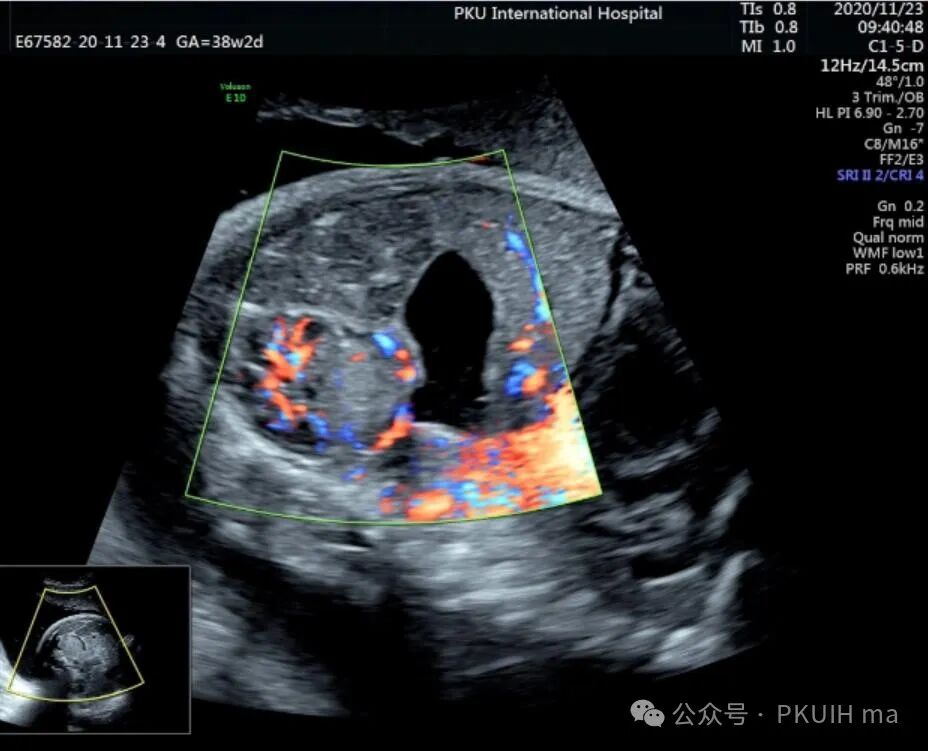

神经母细胞瘤是儿童时期最常见的肿瘤之一,其发病率为1/10,000 -30,000儿童。神经母细胞瘤可在妊娠晚期被诊断出来。产前诊断的肿瘤往往较小,90%涉及肾上腺。囊性和实性区域是典型的,可伴有出血和坏死。囊性病变预后较好。神经母细胞瘤可有微钙化,伴有声影、完整包膜和造成肾脏下移。这些肿瘤可能出现在颈部、胸部或腹部椎旁交感神经节的其他部位。引起气道压迫的宫内病变已有报道。肾上腺肿块伴肝肿大提示神经母细胞瘤的诊断。

上图是一例在孕晚期发现的肾上腺占位,生后病理证实为神经母细胞瘤的患儿,生后及时做了治疗预后非常好,目前宝宝各项指标都很好。

同时在孕晚期也发现孕妇羊水增多

这几年我们在孕晚期发现有3例神经母细胞瘤胎儿,预后都很好。在孕晚期超声中建议常规扫查下胎儿双肾区